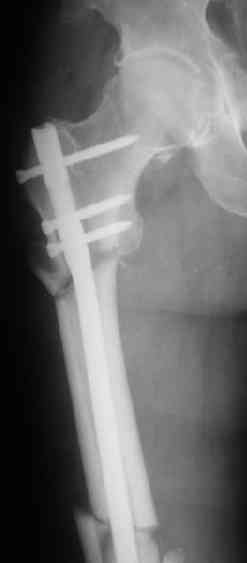

> денамизация - февраль 2006. ( 3 и 4 снимки) на сегодняшний день (снимок 5) беспокоит боли в тбс...

Согласен, что 3,5 см укорочение этим снимкам не соответствует, за счет перелома и деформации - 1,5 см от силы. То есть либо ошибка измерения, либо приводящая контрактура, либо укорочение за счет другого отдела.

Не очень понятно, за счет чего имеется такое значительное (3,5 см) укорочение конечности.

Какие ориентиры берутся при измерении бедра?

Уважаемый ,Ашраф! Считаю в настоящее время основная задача достичь консолидации перелома. Для этого необходимо удалить оставшийся стабилизирующий винт в проксимальном отделе бедра и дать полную нагрузку. Имеющее укорочение на этом периоде компенсировать подбором ортопедической стельки. После курса реабилитации возможно отпадет необходимость восстанавливать длину конечности. С уважением Анатолий.

Внимательно посмотрите на последний снимок. При казалось бы малом размере стержня, резорбции кости вокруг него не отмечается, что говорит о определенной стабильности его в костномозговом канале.